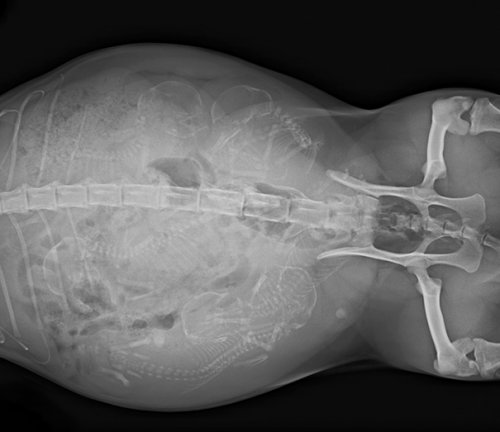

Итак, как выглядят рентгеновские снимки беременных животных:

кошка